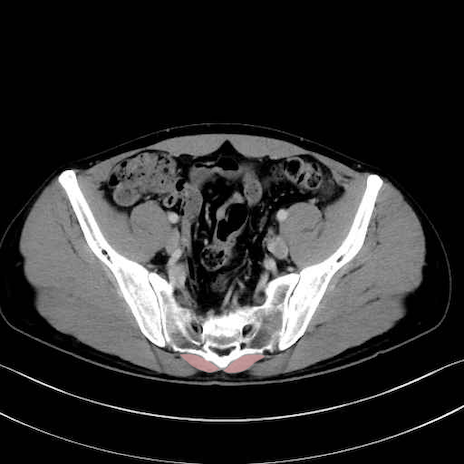

肛門挙筋 (Levator ani)